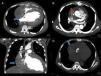

Figure 2.

Contrast-enhanced computed tomography showing a hematoma 9.4cm×8.5cm×5.9cm compressing the right vena cava and right atrium (A, C and D); the collection was caused by an active bleeding point 2.4 cm above the aortic prosthesis (B) in the ascending aorta.

We present a case of a 37-year-old hypertensive male admitted with dyspnea on exertion, orthopnea, paroxysmal nocturnal dyspnea, fatigue and bilateral leg edema. The echocardiogram revealed a dilated left ventricle (diastolic diameter 79 mm, systolic diameter 70 mm) with severely depressed left ventricular function (20% by Simpson's method) and severe aortic regurgitation. He underwent aortic valve replacement and reduction of the ascending aorta. The patient's clinical condition improved significantly but discharge was delayed due to social problems. Three weeks after surgery he suddenly became hypotensive, tachycardic, sweating, pale with cool extremities, and anuric. The electrocardiogram showed sinus tachycardia with left ventricular hypertrophy, and the bedside echocardiogram revealed a medium-sized echogenic mass measuring 9cm×6cm, causing almost complete collapse of the right atrium, and mild (6 mm) circumferential pericardial effusion (Figure 1A–D). Prosthetic function was normal. The emergency computed tomography (CT) scan showed a hematoma measuring 9.4cm×8.5cm×5.9cm compressing the right atrium and an active bleeding point 2.4 cm above the aortic prosthesis in the ascending aorta (Figure 2A and B). The patient was transferred to the cardiothoracic surgery center. Surgical exploration revealed a large organized pericardial hematoma compressing the right atrium. It was removed and the aortic suture was reinforced. The recovery was uneventful. One month later he was clinically well and the echocardiogram showed no pericardial effusion, a functional biological valve and severely depressed left ventricular function.